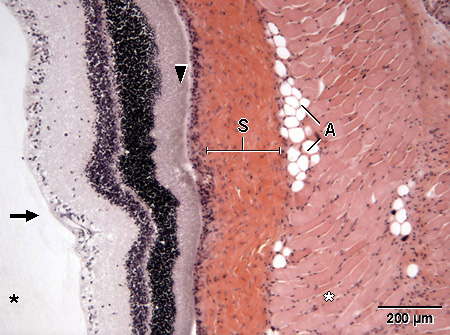

Valomikroskooppikuva rotan silmän verkkokalvosta.H&E

S = kovakalvo, skleera

A = rasvakudos

tähti, musta = lasiainen

tähti, valkoinen = poikkijuovainen lihaskudos (silmänliikuttajalihas)

nuoli = verkkokalvo

nuolenpää = sauva- ja tappisolukerros